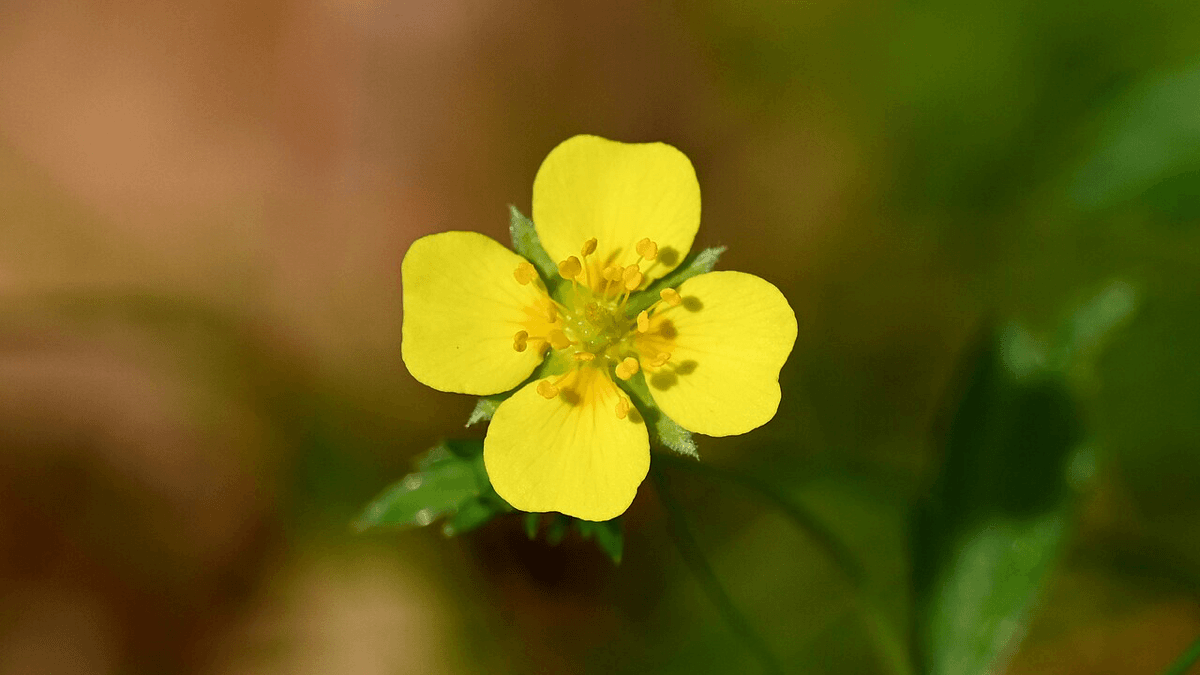

A tormentil, conhecida cientificamente como Potentilla erecta, tem sido utilizada na medicina tradicional por séculos. Suas propriedades terapêuticas despertam o interesse de pesquisadores, especialmente em um cenário de crescente resistência antimicrobiana. Estudos recentes indicam que essa planta pode conter compostos capazes de combater infecções causadas por bactérias resistentes a antibióticos modernos.

Historicamente, a raiz da tormentil foi utilizada na medicina tradicional da Irlanda e da Europa para tratar uma variedade de condições, incluindo feridas, dor de garganta, diarreia e doenças gengivais. Essa utilização sugere que a planta possui compostos com potencial antimicrobiano, o que levou a investigações mais profundas sobre suas propriedades medicinais. O uso de plantas na medicina tradicional é um campo amplamente estudado, como evidenciado em pesquisas sobre medicina tradicional.

Propriedades Antimicrobianas da Tormentil

Pesquisas recentes demonstraram que a tormentil apresenta atividade antimicrobiana significativa, capaz de combater bactérias resistentes. Um estudo recente revelou que extratos da planta inibiram o crescimento de patógenos bacterianos relevantes, incluindo aqueles que causam pneumonia severa e infecções do trato urinário. Os extratos mostraram também eficácia na limitação da formação de biofilmes, que são comunidades bacterianas que dificultam o tratamento com antibióticos.

Pesquisa sobre Compostos Antimicrobianos em Plantas

A busca por novos compostos antimicrobianos tem levado pesquisadores a explorar a biodiversidade vegetal. Em um estudo, foram analisadas mais de 70 espécies de plantas de pântano irlandês, com o objetivo de identificar substâncias que possam combater bactérias multirresistentes. Os testes laboratoriais mostraram que os extratos de tormentil não apenas inibiram o crescimento bacteriano, mas também apresentaram potencial para aumentar a eficácia de antibióticos existentes, como demonstrado em pesquisas que indicam que certos compostos podem tornar os antibióticos mais eficazes.

Potencial de Combinação com Antibióticos Existentes

Estudos indicam que a combinação de extratos de tormentil com antibióticos, como a colistina, pode melhorar a eficácia do tratamento. Embora a colistina, um antibiótico de última linha, não tenha sido suficiente para eliminar as bactérias isoladamente, sua associação com o extrato da tormentil aumentou sua ação antimicrobiana. Essa sinergia entre compostos vegetais e antibióticos representa uma nova abordagem no combate à resistência antimicrobiana, um crescimento global de ameaças à saúde pública.

A tormentil, com suas propriedades antimicrobianas e potencial de combinação com antibióticos, representa uma esperança no combate à resistência bacteriana. A pesquisa contínua sobre seus compostos ativos pode levar ao desenvolvimento de novas estratégias terapêuticas, reafirmando o valor das plantas na medicina moderna.